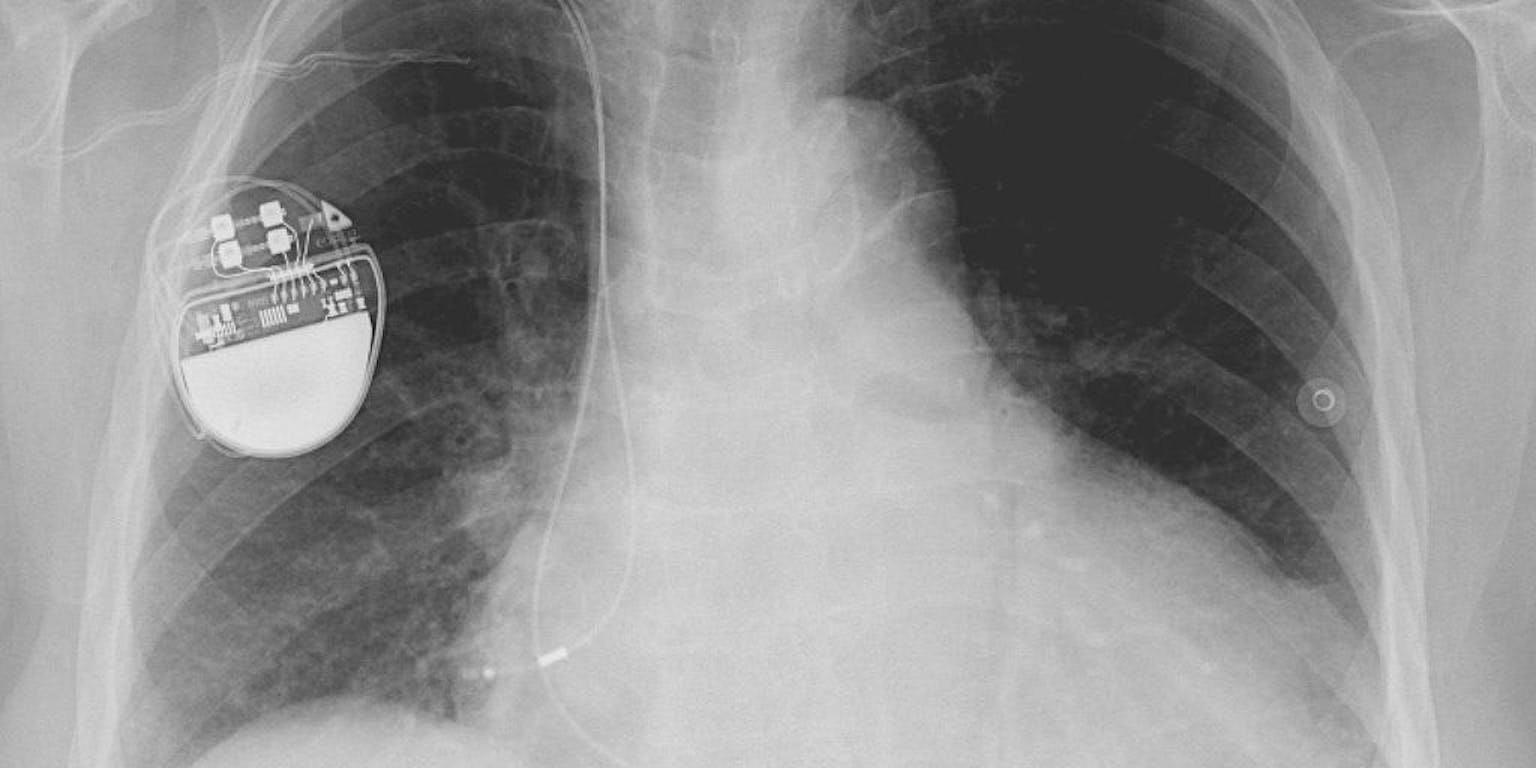

Patiënten met bradycardie hebben een te lage hartslag; hun hart slaat te weinig slagen per minuut. Hierdoor zijn ze sneller moe en vaker duizelig. Omdat medicijnen de hartslag niet veilig op een normaal ritme kunnen brengen, is de enige oplossing voor patiënten met symptomatische bradycardie, een pacemaker. Dit apparaatje verstuurt elektrische signalen naar het hart als het te langzaam slaat, of een slag overslaat.

Helaas komen niet alle patiënten die een pacemaker nodig hebben, hiervoor in aanmerking. Foetussen met een hartblokkade bijvoorbeeld, bij wie de elektrische impulsen niet meer worden doorgegeven van het bovenste naar het onderste gedeelte van het hart. Of volwassenen die een geïmplanteerde pacemaker hebben, maar bij wie deze tijdelijk verwijderd moet worden vanwege een infectie. Zij worden gemiddeld twee tot zes weken met antibiotica behandeld. Meestal krijgen ze dan een tijdelijke pacemaker, maar dat is geen ideale oplossing omdat de kans op een nieuwe infectie dan groot is. Voor deze mensen zou een tijdelijke biologische pacemaker ideaal zijn. Vorige pogingen om zo’n biologische pacemaker te maken, waren nog niet heel succesvol. Maar de poging van Yu-Feng Hu en zijn collega’s van het Cedars-Sinai Heart Institute in Los Angeles lijkt daar verandering in te brengen.